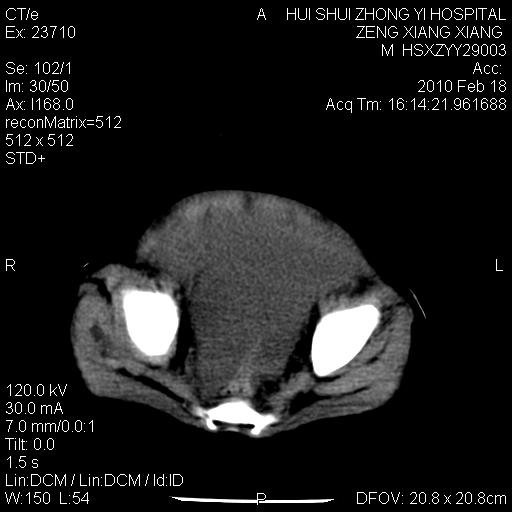

标题: PED3106:男,2岁,腹胀1月。 [打印本页]

标题: PED3106:男,2岁,腹胀1月。

定位腹膜后,肾上腺来源;

定性:恶性神经源性,肾上腺神经节母细胞瘤可能性大。

鉴别:肝母、肾母、肝脏中胚层错构瘤。

依据:年龄、有钙化,肾脏及肝脏受压移位。

肝母细胞瘤可能性大,右肾形态大体可见,不支持肾母细胞瘤,右肾移位不明显,肾上腺神经母细胞瘤可能性不大。